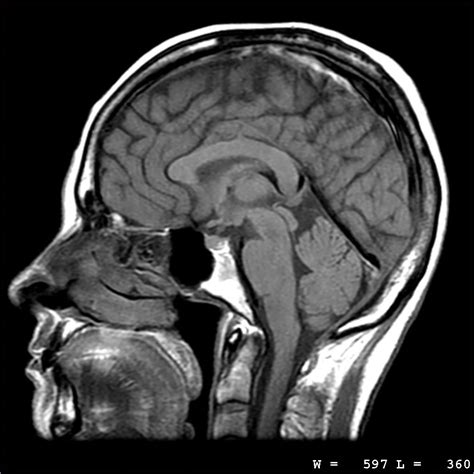

First off, let’s get a handle on what an MRI actually is . MRI stands for Magnetic Resonance Imaging . It’s a sophisticated medical imaging technique that uses strong magnetic fields and radio waves to create detailed images of the organs and tissues within your body. Unlike X-rays or CT scans, MRIs don’t use ionizing radiation, making them a safer option for repeated imaging.

So, how does this magical machine work? The MRI scanner is a large, tube-shaped device. You’ll lie inside it while the machine generates a strong magnetic field. This field aligns the protons in your body. Then, radio waves are emitted, which cause these protons to produce signals. These signals are detected by the scanner and processed by a computer to create cross-sectional images of your body. These images can be viewed from different angles, providing a comprehensive view of the area being examined.

Why would your doctor recommend an MRI? Well, MRIs are incredibly versatile and can be used to diagnose a wide range of conditions. They’re particularly good at imaging soft tissues, such as the brain, spinal cord, muscles, ligaments, and tendons. This makes them invaluable for diagnosing conditions like brain tumors, spinal cord injuries, torn ligaments, and other musculoskeletal problems. Plus, because they don’t use radiation, they’re safe for pregnant women and children (though special precautions may be necessary).

Brain MRI is used to image the brain and surrounding structures. It can help diagnose conditions such as brain tumors, stroke, multiple sclerosis, and Alzheimer’s disease. Many facilities in Newport Beach offer advanced brain MRI techniques, such as diffusion tensor imaging (DTI) and functional MRI (fMRI), which provide even more detailed information about brain structure and function.